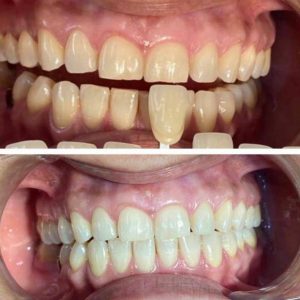

Tratamientos Ortodoncia Blanqueamiento dental Zoom Contacto 72 2795 9597 Marcar Ahora Envia whatsapp Visita nuestro facebook